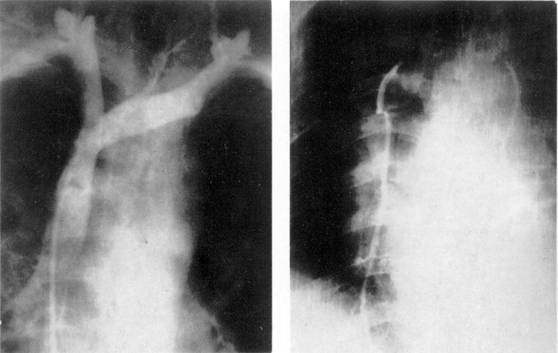

Диагностические изображения синдрома бронхиальной непроходимости